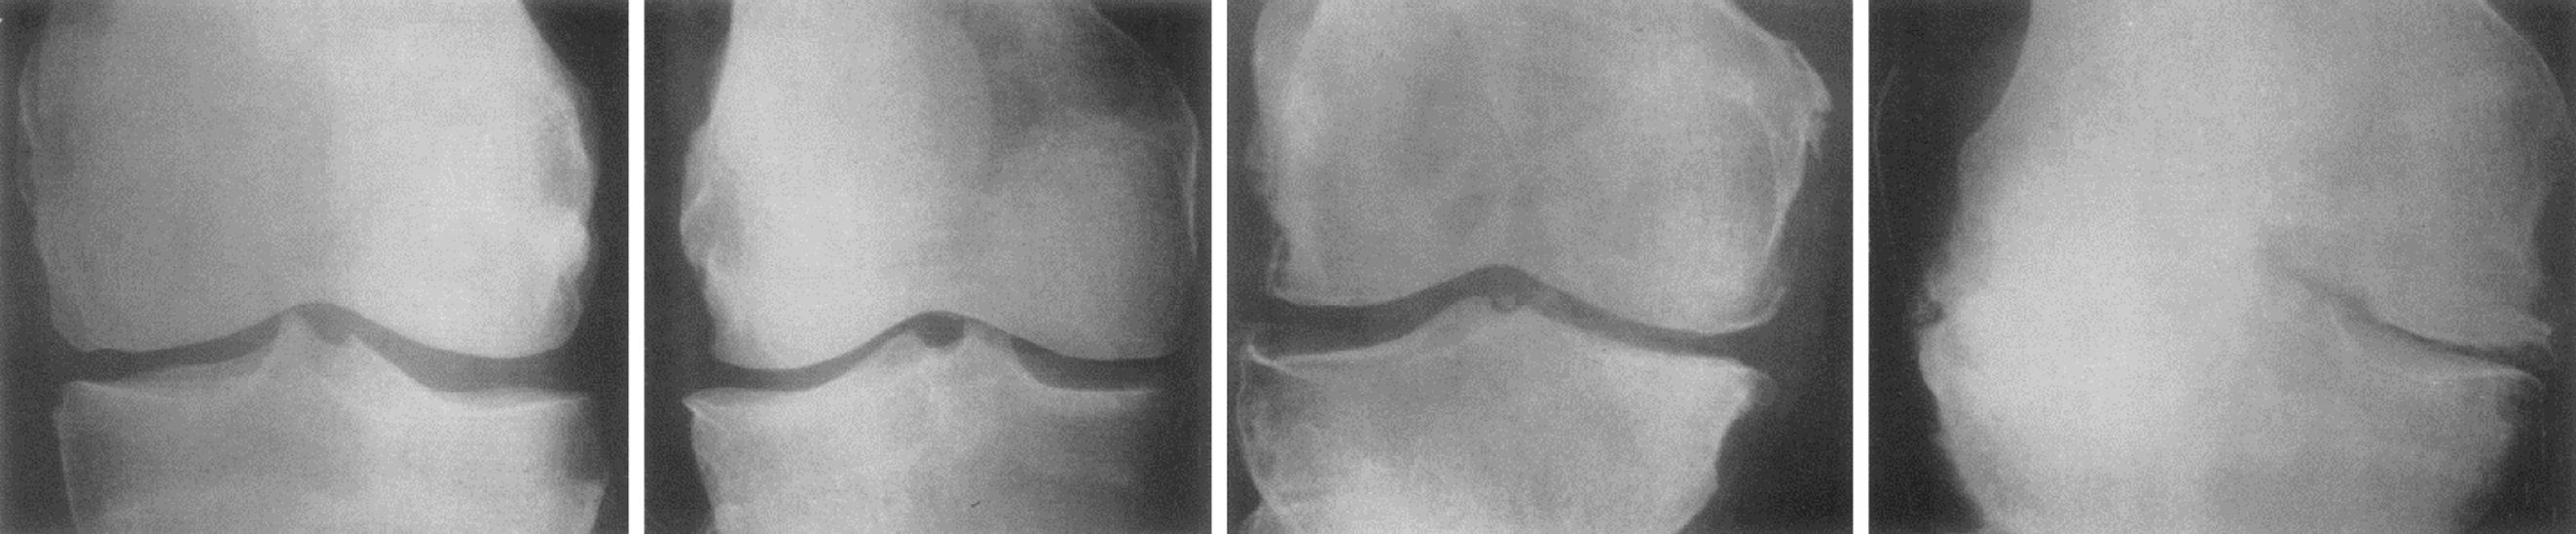

Symptomatic osteoarthritis is characterized by the combination of radiographic evidence of OA along with clinical manifestations such as joint pain, stiffness, and functional limitations. It is important to note that not all the patients with radiographic osteoarthritis will develop symptomatic disease. Diagnosis of PTOA is done by history of trauma to the knee joint along with joint features like pain, swelling, and stiffness. Imaging studies such as magnetic resonance imaging (MRI) and X-ray can assess the extent and type of injury in the joint. The loss of cartilage and degeneration of joint is best visualized by these imaging studies. X-ray has been the investigation of choice to diagnose osteoarthritis. According to Kellgren and Lawrence in 1957, the X-ray findings of OA are categorized into four grades ranging from I to IV based on the radiological visualization of joint width and joint surface destruction (Figure 1 and Table 1). X-ray is cost-effective and readily available as an out-patient investigation tool. The KL scale does not consider the symptoms when defining the severity of OA; however, early stages do not present with clinical symptoms[9,10].

Figure 1

Figure 1 Kellgren Lawrence Grades 1 to 4 from left to right[10]. Citation: Kellgren JH, Lawrence JS. Radiological assessment of osteo-arthrosis. Ann Rheum Dis 1957; 16: 494–502 Copyright© The Authors 1957. Published by Elsevier. The authors have obtained the permission for figure using from the Elsevier (Supplementary material).